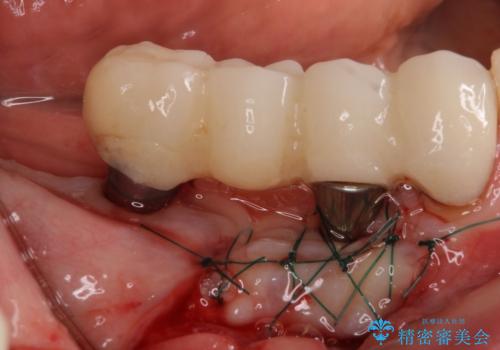

下顎右側は骨造成を併用してインプラント治療を行い、その他の奥歯もインプラントや歯周外科処置を併用して補綴治療を進め、最後に前歯部の欠けてしまったセラミッククラウンを作り替えることとしました。